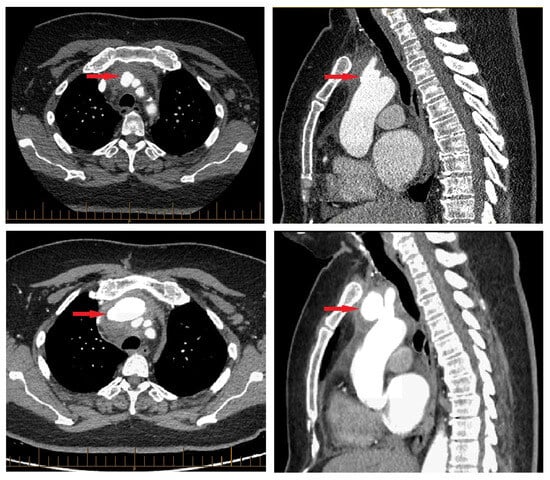

CT revealed a pseudoaneurysm (7 × 5.5 mm) at the common origin of the brachiocephalic trunk, and the left common carotid artery was incidentally found (Figure 1). Surrounding periaortic fat stranding and the presence of axillary and retro-pectoral lymph nodes suggested an infectious process. A transthoracic echocardiogram demonstrated normal cardiac chamber dimensions, preserved systolic and diastolic function (left ventricular ejection fraction 60–65%), and mild degenerative valvular changes without intra-cardiac vegetations or significant valvulopathy.

Inflammatory markers remained elevated but gradually declined, as did WBCs. Troponins peaked mildly within 5 days of admission (34.0 ng/L) and eventually normalized, as did TSH by discharge. After a satisfactory decline in infectious and inflammatory biological parameters under intravenous piperacillin–tazobactam, the decision was made to pursue outpatient parenteral antibiotics. However, a CT angiogram performed before the patient’s discharge three weeks after admission revealed an interval increase in the mycotic aneurysm (41 × 26 mm) (Figure 1). In light of this change, a staged surgical intervention was undertaken 2 weeks later.

The patient was then transferred to the intensive care unit in stable condition, where she eventually progressed to the surgical ward and continued to progress favourably. Post-operative imaging (CT angiography) performed on day 12 post-operatively demonstrated a circumferential hematoma around the ascending aorta and hemiarch graft measuring 20 mm in thickness, with internal air bubbles attributed to surgical changes. Follow-up imaging confirmed the resolution. The patient completed a full course of intravenous antibiotics (ceftriaxone for 6 weeks post-operatively) with good recovery at three months post-operatively. Her total hospitalization at our center lasted 55 days, and she was discharged 18 days after surgery, returning to her hospital of origin to complete treatment.

Figure 1. Initial finding of pseudoaneurysm (red, top row) and sudden enlargement (bottom row).